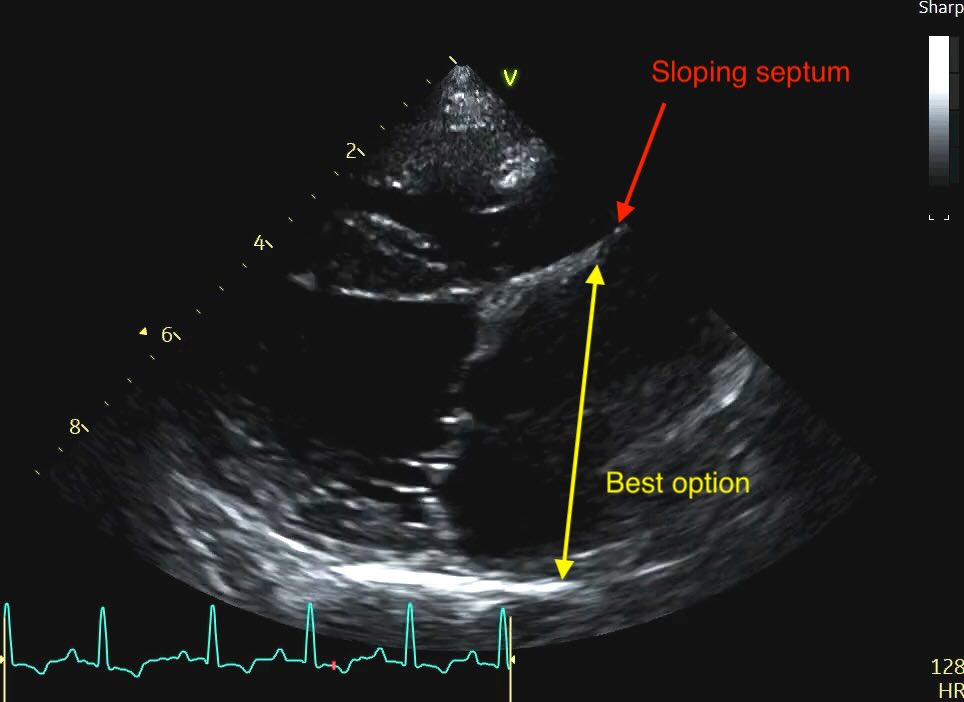

The Problem of the “Bowed” Septum

Sometimes you’ll see a distended or “bowed” interatrial septum, often sloping up to the right on the view merging with some dilated pulmonary veins. In a volume-overloaded heart, the high pressure in the left atrium often causes the septum to bulge significantly into the right atrium.

Clinical Recommendation: When the septum is distended, do not measure from the most “sunken” point. Instead, measure from the middle of the septal curvature to the posterior wall, ensuring your line remains strictly parallel to the mitral annulus. Subjectively, a septum that loses its horizontal orientation and “blows out” into the right heart is a strong red flag for elevated filling pressures, even if your linear measurement is borderline.